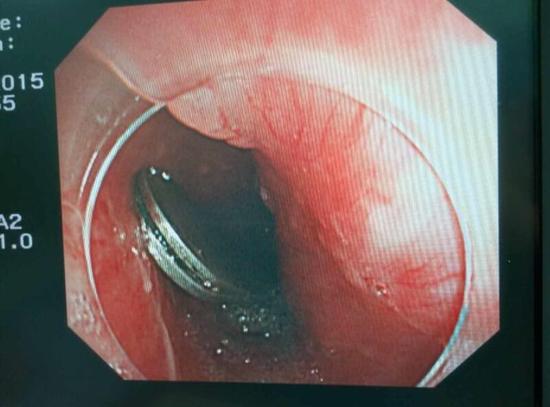

醫(yī)生從華先生胃里取出的鑷子和打火機(jī)

手術(shù)中,范醫(yī)生通過(guò)胃鏡準(zhǔn)確發(fā)現(xiàn)了胃里的鑷子。但讓他驚訝的是,在華先生胃底竟然還躺著三個(gè)被腐蝕了的打火機(jī),打火機(jī)的金屬部件都已經(jīng)不見(jiàn)了。

隨后,范醫(yī)生先用圈套器套取出了長(zhǎng)10厘米的鑷子,再一個(gè)一個(gè)地取出了打火機(jī)。整個(gè)取出過(guò)程小心謹(jǐn)慎而又一氣呵成,只用了不到10分鐘。